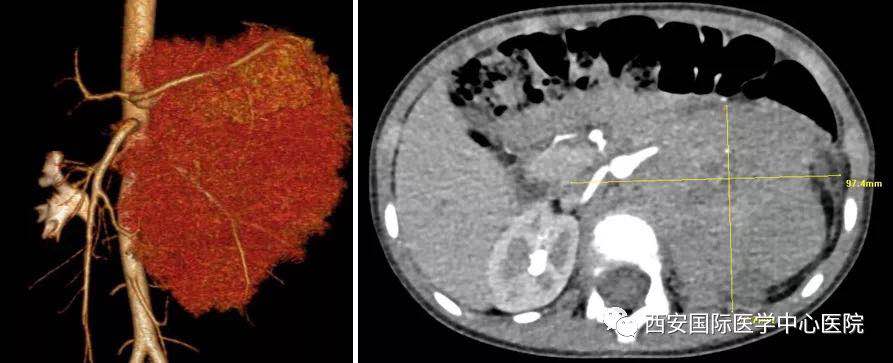

入院后,楊增悅主任仔細詢問病史、查閱影像學(xué)資料,第一時間為依依安排骨髓穿刺活檢,最終確診為:腹膜后神經(jīng)母細胞瘤(Ⅳ期/L2)。CT顯示腫瘤巨大,侵及腹主動脈、腹腔干、腸系膜上動脈、雙腎動脈、腸系膜下動脈、下腔靜脈、雙腎靜脈、左腎及腎上腺、胰十二指腸、脾臟、結(jié)腸脾曲;腹膜后多發(fā)淋巴結(jié)轉(zhuǎn)移、骨轉(zhuǎn)移。骨穿病檢示:神經(jīng)母細胞瘤骨髓轉(zhuǎn)移,腫瘤細胞占90.5%。經(jīng)過科室團隊討論后決定,先行新輔助化療后再進行手術(shù)治療。

經(jīng)6個周期的化療后,依依的骨髓腫瘤細胞由90.5%轉(zhuǎn)陰。

經(jīng)多學(xué)科會診討論,泌尿外科專家團隊決定為依依行腹膜后神經(jīng)母細胞瘤切除術(shù)。一切準備工作就緒,7月20日,在麻醉手術(shù)中心柴偉主任及其團隊的有力保障下,泌尿外科楊增悅教授主持指導(dǎo),舒濤、王東,陳勇等協(xié)助完成。手術(shù)過程順利,術(shù)后患兒生命體征平穩(wěn),已返回泌尿外科普通病區(qū)進一步康復(fù)。